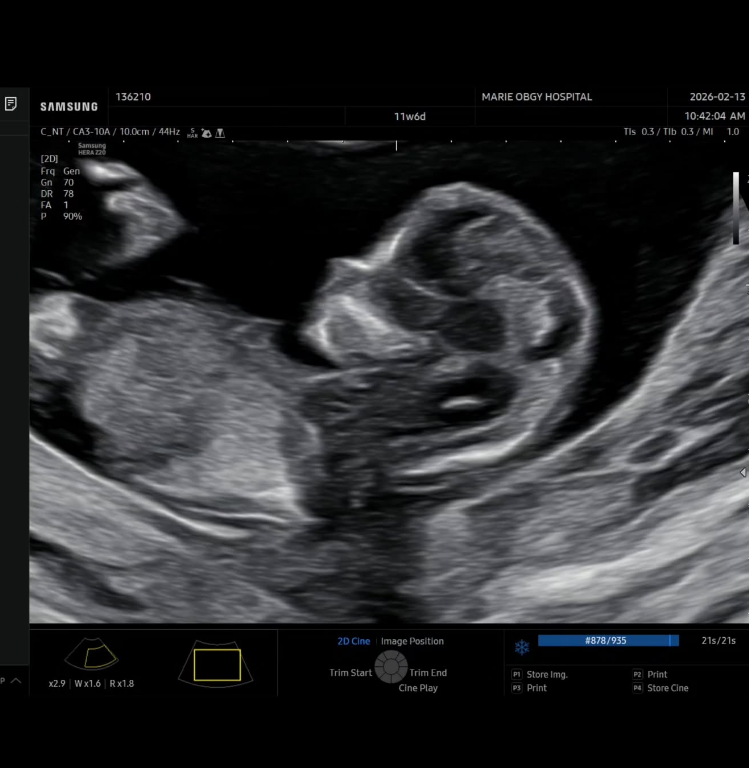

17일 김무영은 자신의 SNS에 “우리 가족에게 찾아온 또 하나의 선물, 루이와 루디에 이어 세 번째 기적이 찾아왔습니다”라는 글과 함께 초음파 사진을 공개했다.

이어 그는 “아직은 누굴 닮았는지, 성별이 무엇인지 모든 게 신비롭기만 하네요. 건강하게만 만나자, 우리 막내야!”라고 덧붙였다.